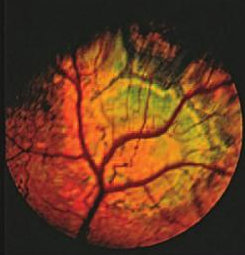

In multifocal RD, "folds" appear in the inner retinal layer, called

retinal folds.

They vary in number, from one to several. In the "geographic"

form of multifocal retinal dysplasia (MRD), there are larger areas of

defective retinal

development. They appear as irregular or horseshoe-shaped areas. (See the eye of a CKCS with geographic retinal dysplasia, at

below left.) In the severe form of dysplasia, known as retinal detachment, the

retinal layers do not come together at all.

Retinal folds represent small blind spots which are probably not even noticed by the dog. However, geographic dysplasia may lead to large deficits in the visual field.